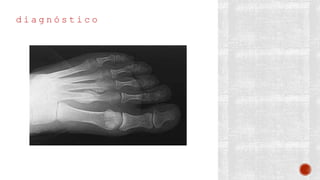

d i a g n ó s t i c o

¬ Clínico

¬ Radiológico

- AP

- Lateral

- Oblicua